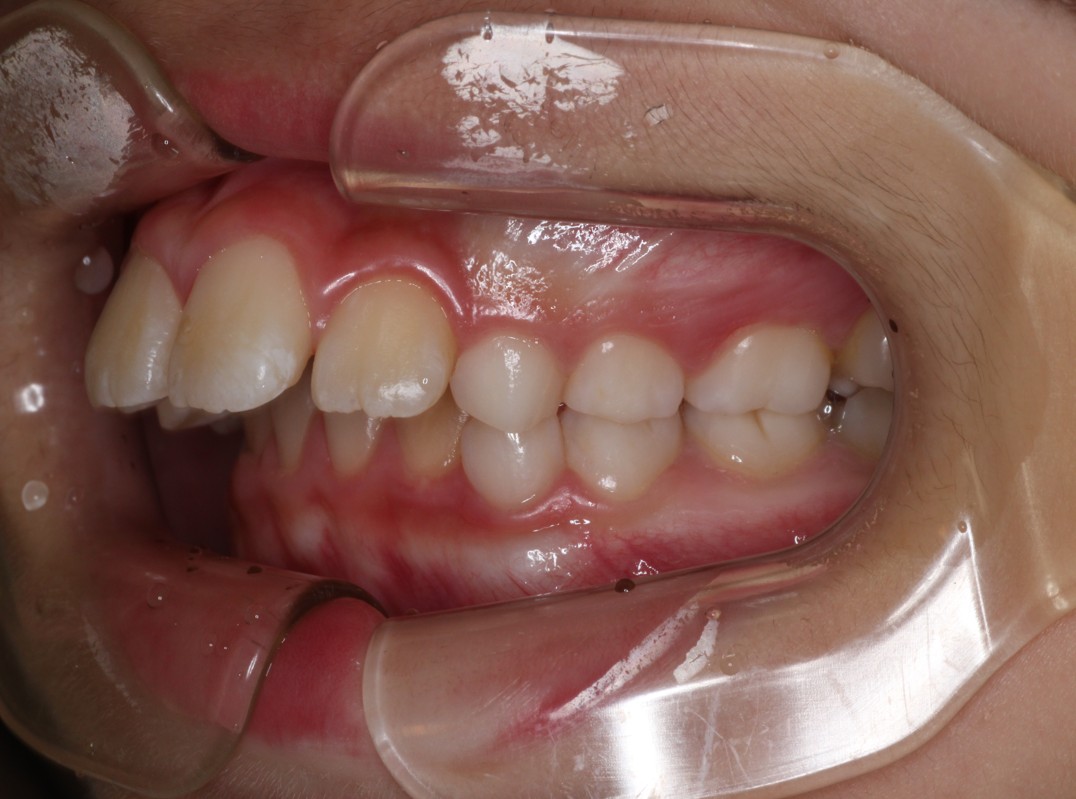

治療前

出っ歯を治したい。永久歯が生えず不安に思っている。 |

出っ歯と下の永久歯が生えるスペースがないことを主訴にご来院されました。 |